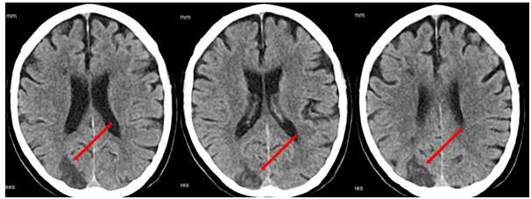

TAC de cráneo simple (a las 48 h de evolución) (Figura 1): Se observa imagen hipodensa de aspecto vascular en región occipital que se extiende hasta región parietal posterior, territorio limítrofe de ACM y ACP derechas. Las imágenes corresponden a un infarto isquémico en evolución.

Hablamos de un varón de 68 años de edad, hipertenso, diabético y con dislipidemia, que debuta con un cuadro clínico de hemiparesia izquierda, apraxia cinética y hemianopsia homónima; focalidad neurológica que habitualmente corresponde y es atribuida a territorio vascular de la ACM del hemisferio derecho, asociado con una ausencia de flujo en la carótida interna proximal homónima evidenciada en el Doppler. Estos hallazgos sugieren plantear con mucha fuerza en sus inicios, un infarto en el territorio de la ACM derecha. Sin embargo, los estudios posteriores (TAC de cráneo a las 48 h de evolución) (Figura 1) imponen reconsiderar el diagnóstico y valorar la posibilidad de variantes anatómicas en la circulación intracraneal, comprobando estos últimos con el estudio de Angio-TC (Figura 2).